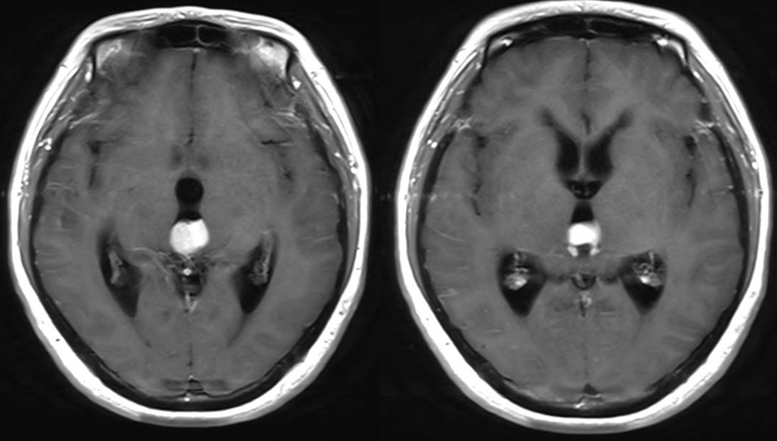

诊治过程:结合患者临床表现及影像学表现,初步诊断考虑为三脑室后部胶质瘤合并梗阻性脑积水可能性大,术前制定的手术方案为经胼胝体穹隆间入路三脑室后部肿瘤切除术+脑室镜辅助下三脑室底造瘘术,该手术方式既可切除肿瘤获取病理,同时可行三脑室底造瘘解决脑积水症状。术中采用冠状缝前额部弧形切口,术中沿纵裂牵开双侧大脑半球,探及胼胝体,沿中线切开胼胝体,分离双侧透明隔,暴露双侧穹隆,严格沿中线分离双侧穹隆,保护两侧穹隆的完整,避免引起术后的记忆力障碍,牵拉开双侧穹隆,进入中间帆,显露并分离双侧大脑内静脉继续向下,经脉络膜隔进入三脑室,完全显露肿瘤组织,肿瘤组织呈灰红色,血供极其丰富,与中脑黏连紧密,仔细分离,分块全切肿瘤,双侧大脑内静脉及中脑保护良好,中脑导水管通畅。肿瘤完全切除后,考虑到术后局部粘连、肿瘤复发等因素可能导致脑积水不缓解,置入脑室镜向前方探查,小心切开中间块,在双侧乳头体与漏斗隐窝之间,行三脑室底部造瘘并打开Liliequist膜及基底动脉旁蛛网膜,确认漏口通畅且与脚间池相通。患者术后恢复过程平稳,颅脑MRI提示肿瘤切除满意,脑积水缓解。术后病理结果示:中枢神经细胞瘤(2级)。术后予以放疗GTV 5400cGy、PTV 5040cGy,28f。现术后已3年,复查未见肿瘤复发,脑积水已完全缓解。